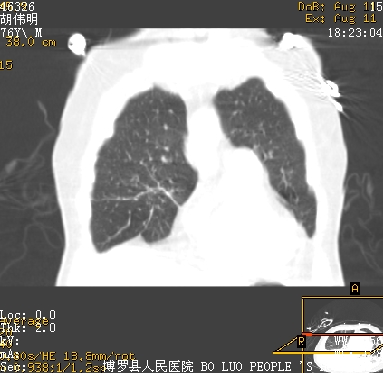

11号ct

1)两肺感染性病变(右肺下叶肺脓肿可能)。2)双侧胸腔积液,以右侧为甚。

混合型肺水肿合并感染,肺膨胀不全,胸膜肥厚粘连包裹,同时肺内有陈旧性病灶。注意复查

ards,肺感染性病变,右下叶实变,双侧胸腔积液,右侧为著,叶间胸膜积液,右上肺陈旧性tb纤维灶,左室大。